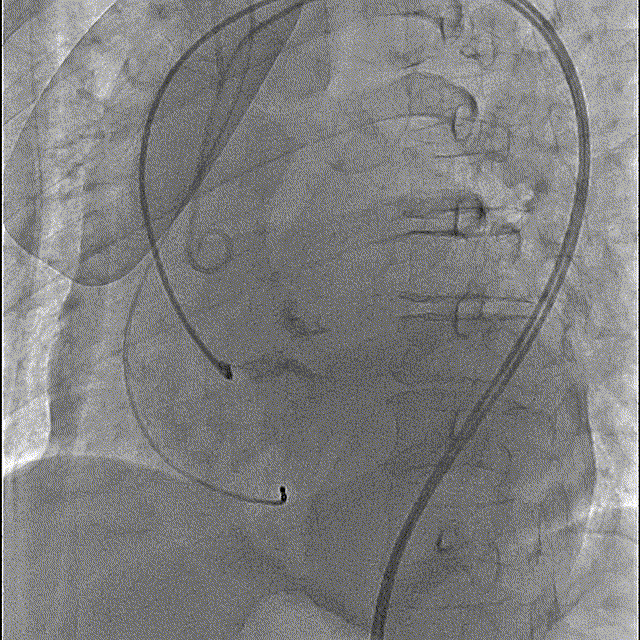

瓣膜开花造影

瓣膜工作位造影